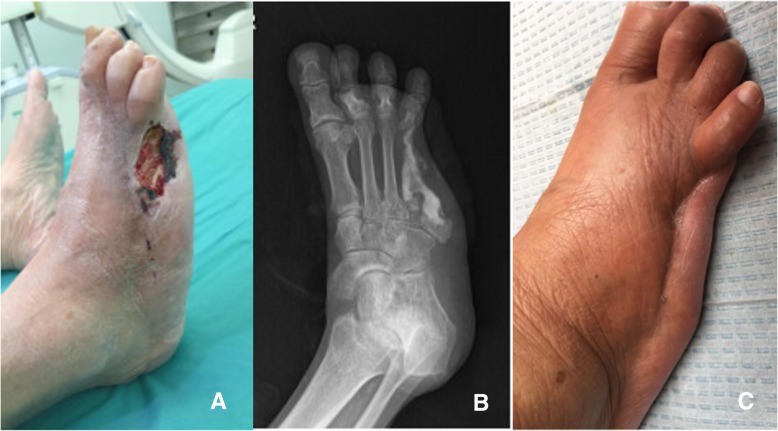

Fig. 1.

A patient with the fourth infected metatarsal (the fifth phalanx and metatarsal had been resected 5 years ago) were resected to the base of metatarsal before the vancomycin-impregnated calcium sulfate was injected into the dead space. a The presentation of wound before the operation. b The X-ray presentation 3 days after operation. c The ulcer had healed and no symptoms of osteomyelitis were presented 1 year after operation